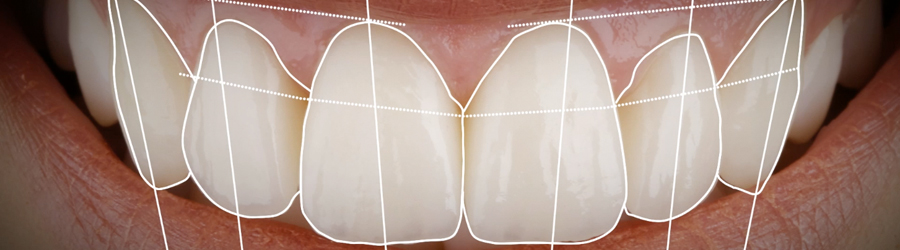

Consiste em um ensaio fotográfico prévio onde são realizados imagens digitais em alta resolução do sorriso, dentes e face do paciente. Essas imagens são inseridas em um software e analisadas minunciosamente.

Após analise fotográfica, um projeto de um novo sorriso é desenhado, individualmente, em computador e analisado digitalmente, podendo ser compartilhado e visualizado pelo paciente e dentista antes de ser posto em prática.

O grande objetivo do DSD é criar um design de sorriso que esteja de acordo com as necessidades funcionais, estéticas e até emocionais do paciente, como ter um sorriso mais delicado, mais extrovertido ou mais intenso. Palavras que se materializam na transportação virtual do sorriso, antecipando o resultado esperado.